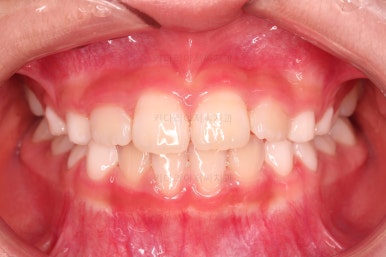

4. 마무리

부산어린이교정 키다리아저씨치과에서 앵글씨 3급 부정교합 및 반대교합이 잘 개선되었습니다.

심지어는 치열을 정교하게 맞추는 기능이 있는 장치는 아니지만, 자연스럽게 맹출 경로를 잡아줌으로써 앞니 치열도 매우 고른 양상이 되었습니다.

전후 비교해 보겠습니다.

옆라인도 아랫입술이 불룩해 보이던 양상에서 많이 좋아졌고요.

웃을 때 드러나는 치열도 좋아졌네요.